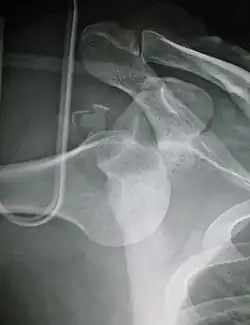

| Anterior dislocation of the left shoulder. | |

In over 95% of shoulder dislocations, the humerus is displaced anteriorly.[8] In most of those, the head of the humerus comes to rest under the coracoid process, referred to as sub-coracoid dislocation. Sub-glenoid, subclavicular, and, very rarely, intrathoracic or retroperitoneal dislocations may also occur.[9]

Anterior dislocations are usually caused by a direct blow to, or fall on, an outstretched arm. The person typically holds his/her arm externally rotated and slightly abducted.[10]

An anterior dislocation of the shoulder